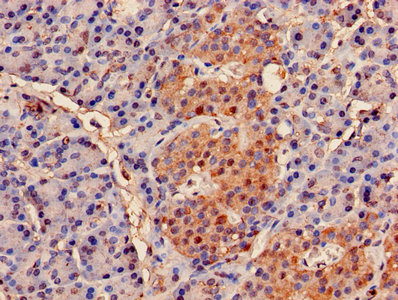

IHC image of CSB-PA01385A0Rb diluted at 1:500 and staining in paraffin-embedded human kidney tissue performed on a Leica BondTM system. After dewaxing and hydration, antigen retrieval was mediated by high pressure in a citrate buffer (pH 6.0). Section was blocked with 10% normal goat serum 30min at RT. Then primary antibody (1% BSA) was incubated at 4°C overnight. The primary is detected by a biotinylated secondary antibody and visualized using an HRP conjugated SP system.

Immunohistochemistry of paraffin-embedded human pancreatic tissue using CSB-PA01385A0Rb at dilution of 1:100